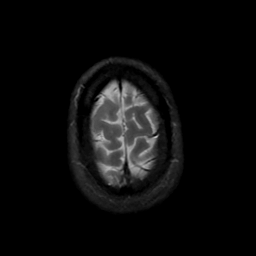

MR Study #16, June 23, 1991 -- Slice #45

[Home][Help][Clinical][Tour 1][Tour 2] Slice 45